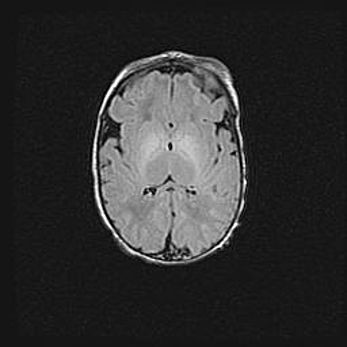

Множественные кисты обоих полушарий головного мозга, наибольшая из них в правой затылочной области. Ассиметричная атрофическая гидроцефалия.

Возраст: 7 месяцев

Вес: 5660 г

Пол: мужской

Окружность головы: 41,5 см

Срок гестации: 28-29 недель

Кисты головного мозга развиваются в результате многоочаговых некрозов вещества мозга и возникают вследствие перенесенной перинатальной инфекции, менингитов, энцефалитов, асфиксии, родовой травмы, расстройств мозгового кровообращения различного генеза. Образованию кист в веществе головного мозга плодов и новорожденных способствуют такие факторы, как высокое содержание в нем воды, недостаточная (или отсутствие) миелинизация и слабая астроглиальная реакция на повреждение.

Кисты могут сочетаться с гидроцефалией и другими поражениями головного мозга.